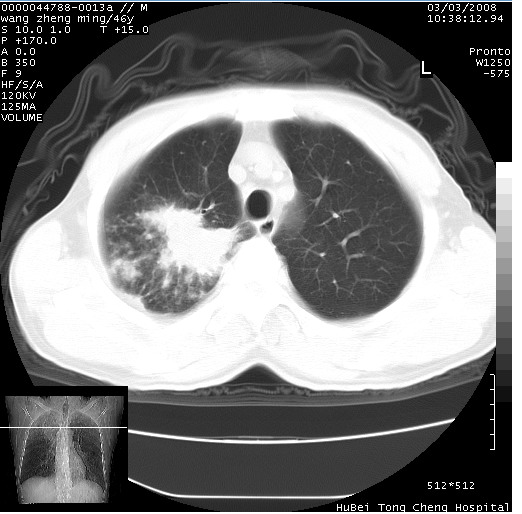

以下是引用卜一在2008-3-22 1:37:00的发言:[br]右肺实质性肿块,边缘不整,明显见毛刺征 分叶征及胸膜凹陷征,右上叶支气管明显变窄,远端散在的片状 斑片状实变影。另:左肺门较大肿块,支气管受累 变窄,远侧见阻塞性肺炎。纵隔内见肿大淋巴结。多考虑:右肺周围性肺癌伴左肺门 纵隔淋巴结转移!